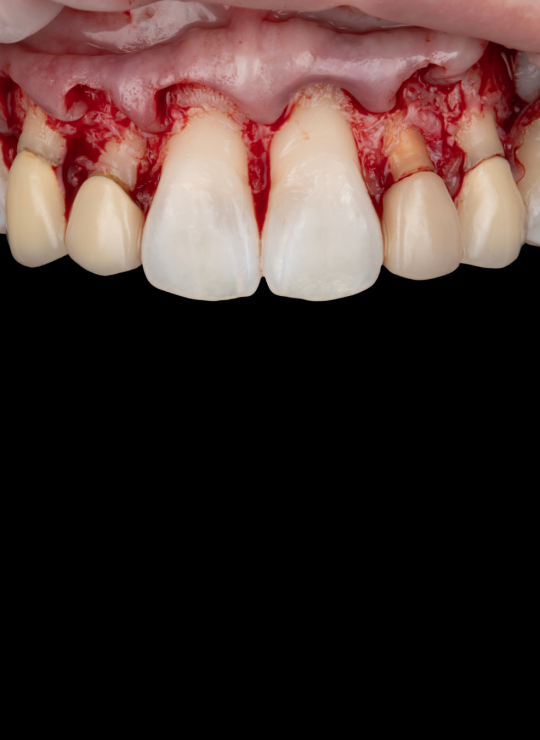

A Crown Lengthening Masterclass

Surgical techniques for aesthetic crown lengthening: flap design, bone recontouring, and suturing

Case demonstrations: gummy smile correction, uneven gingival margins, anterior restorative integration (veneers, crowns)